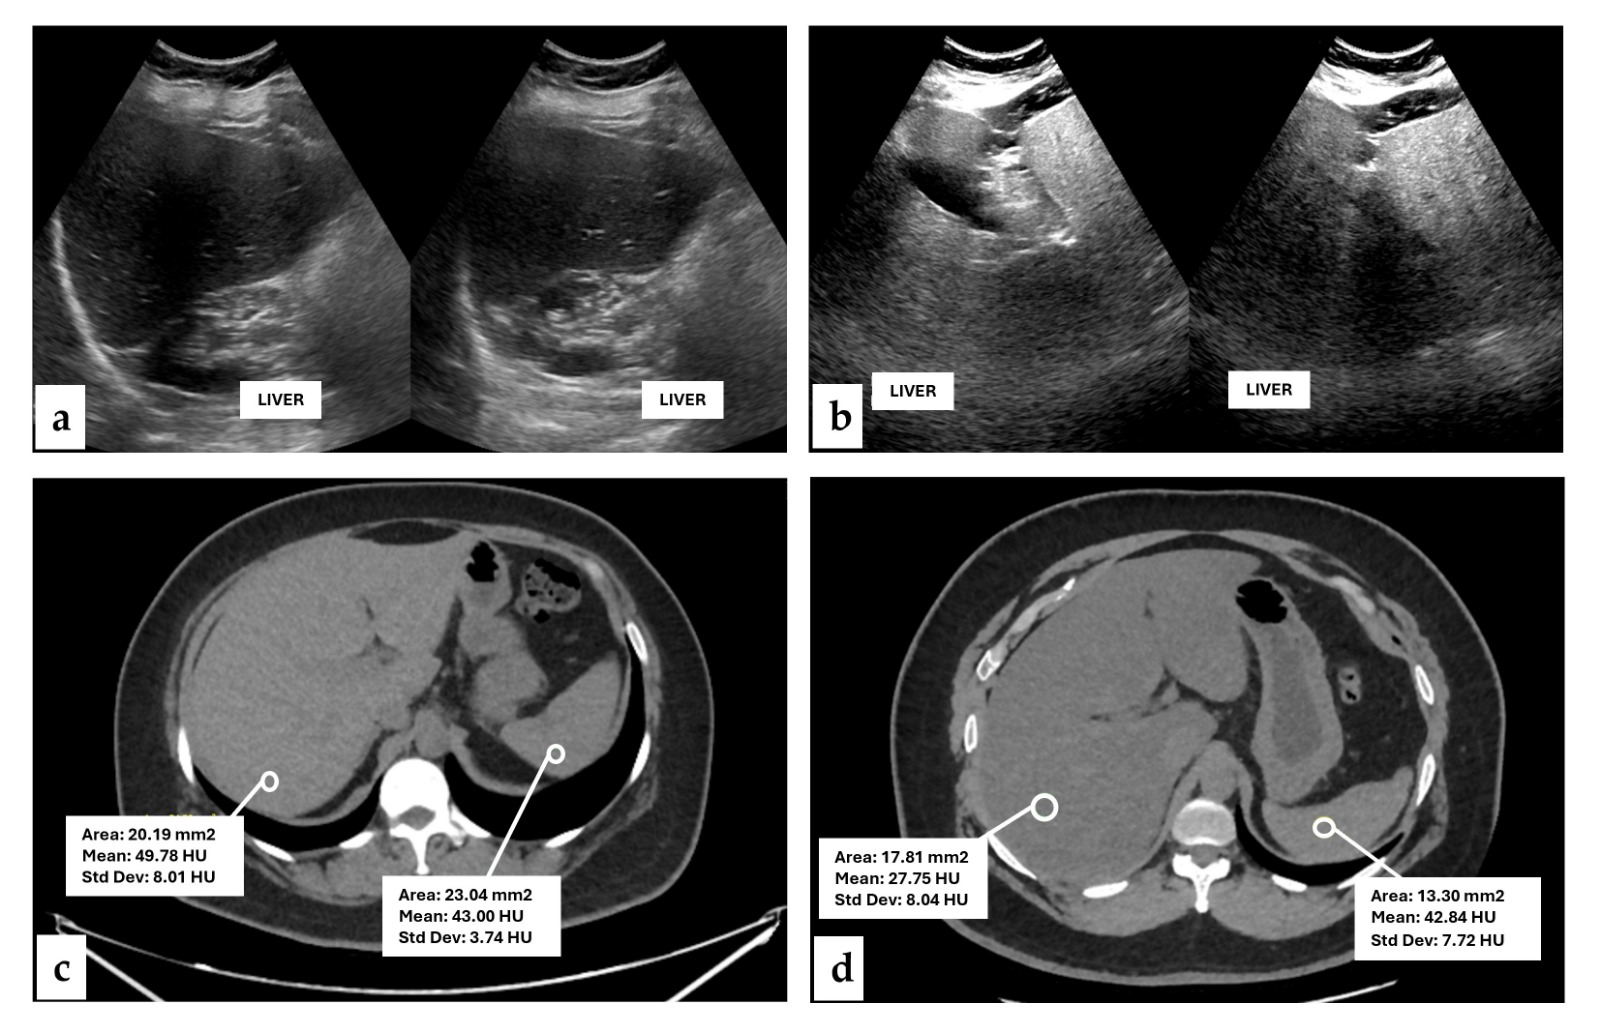

2.3. Radiological Studies for Assess Hepatic Steatosis

| CT | Computed tomography |

| USG | Ultrasonograpy |

| HU | Hounsfield units |